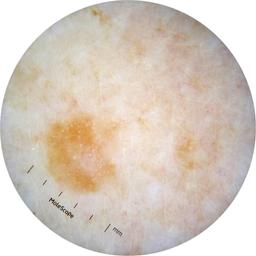

ISIC_2631400

MEL-SELF Trial, https://www.sydney.edu.au/medicine-health/our-research/research-centres/melself-project.html

Clinical

Field Value

acquisition_day 146

age_approx 70

anatom_site_1 Lower extremity

anatom_site_general lower extremity

concomitant_biopsy False

diagnosis_1 Benign

diagnosis_confirm_type single image expert consensus

family_hx_mm True

fitzpatrick_skin_type I

image_manipulation instrument only

image_type dermoscopic

lesion_id IL_2672529

patient_id IP_8223109

personal_hx_mm True

sex female